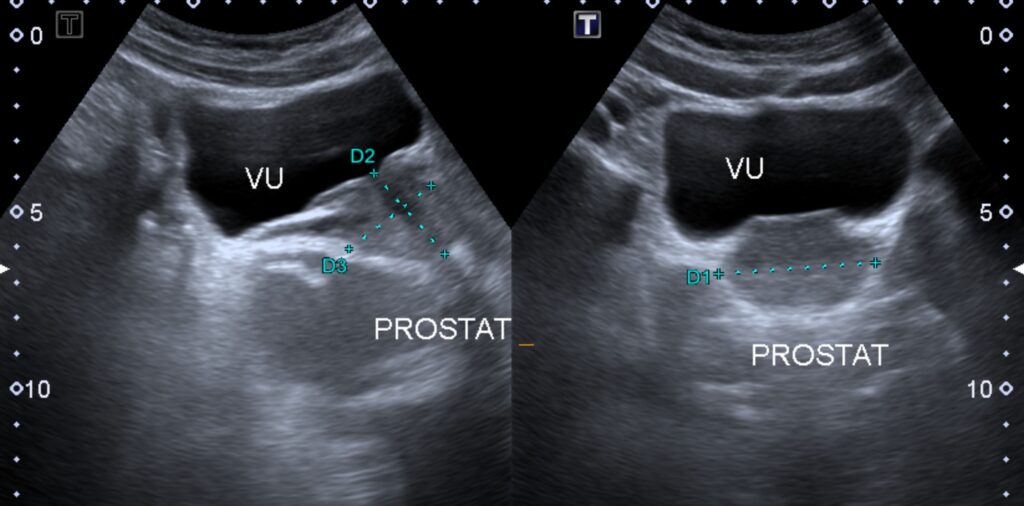

- TRUS: Measures prostate size (crucial for UroLift's $\le 60$ g target).